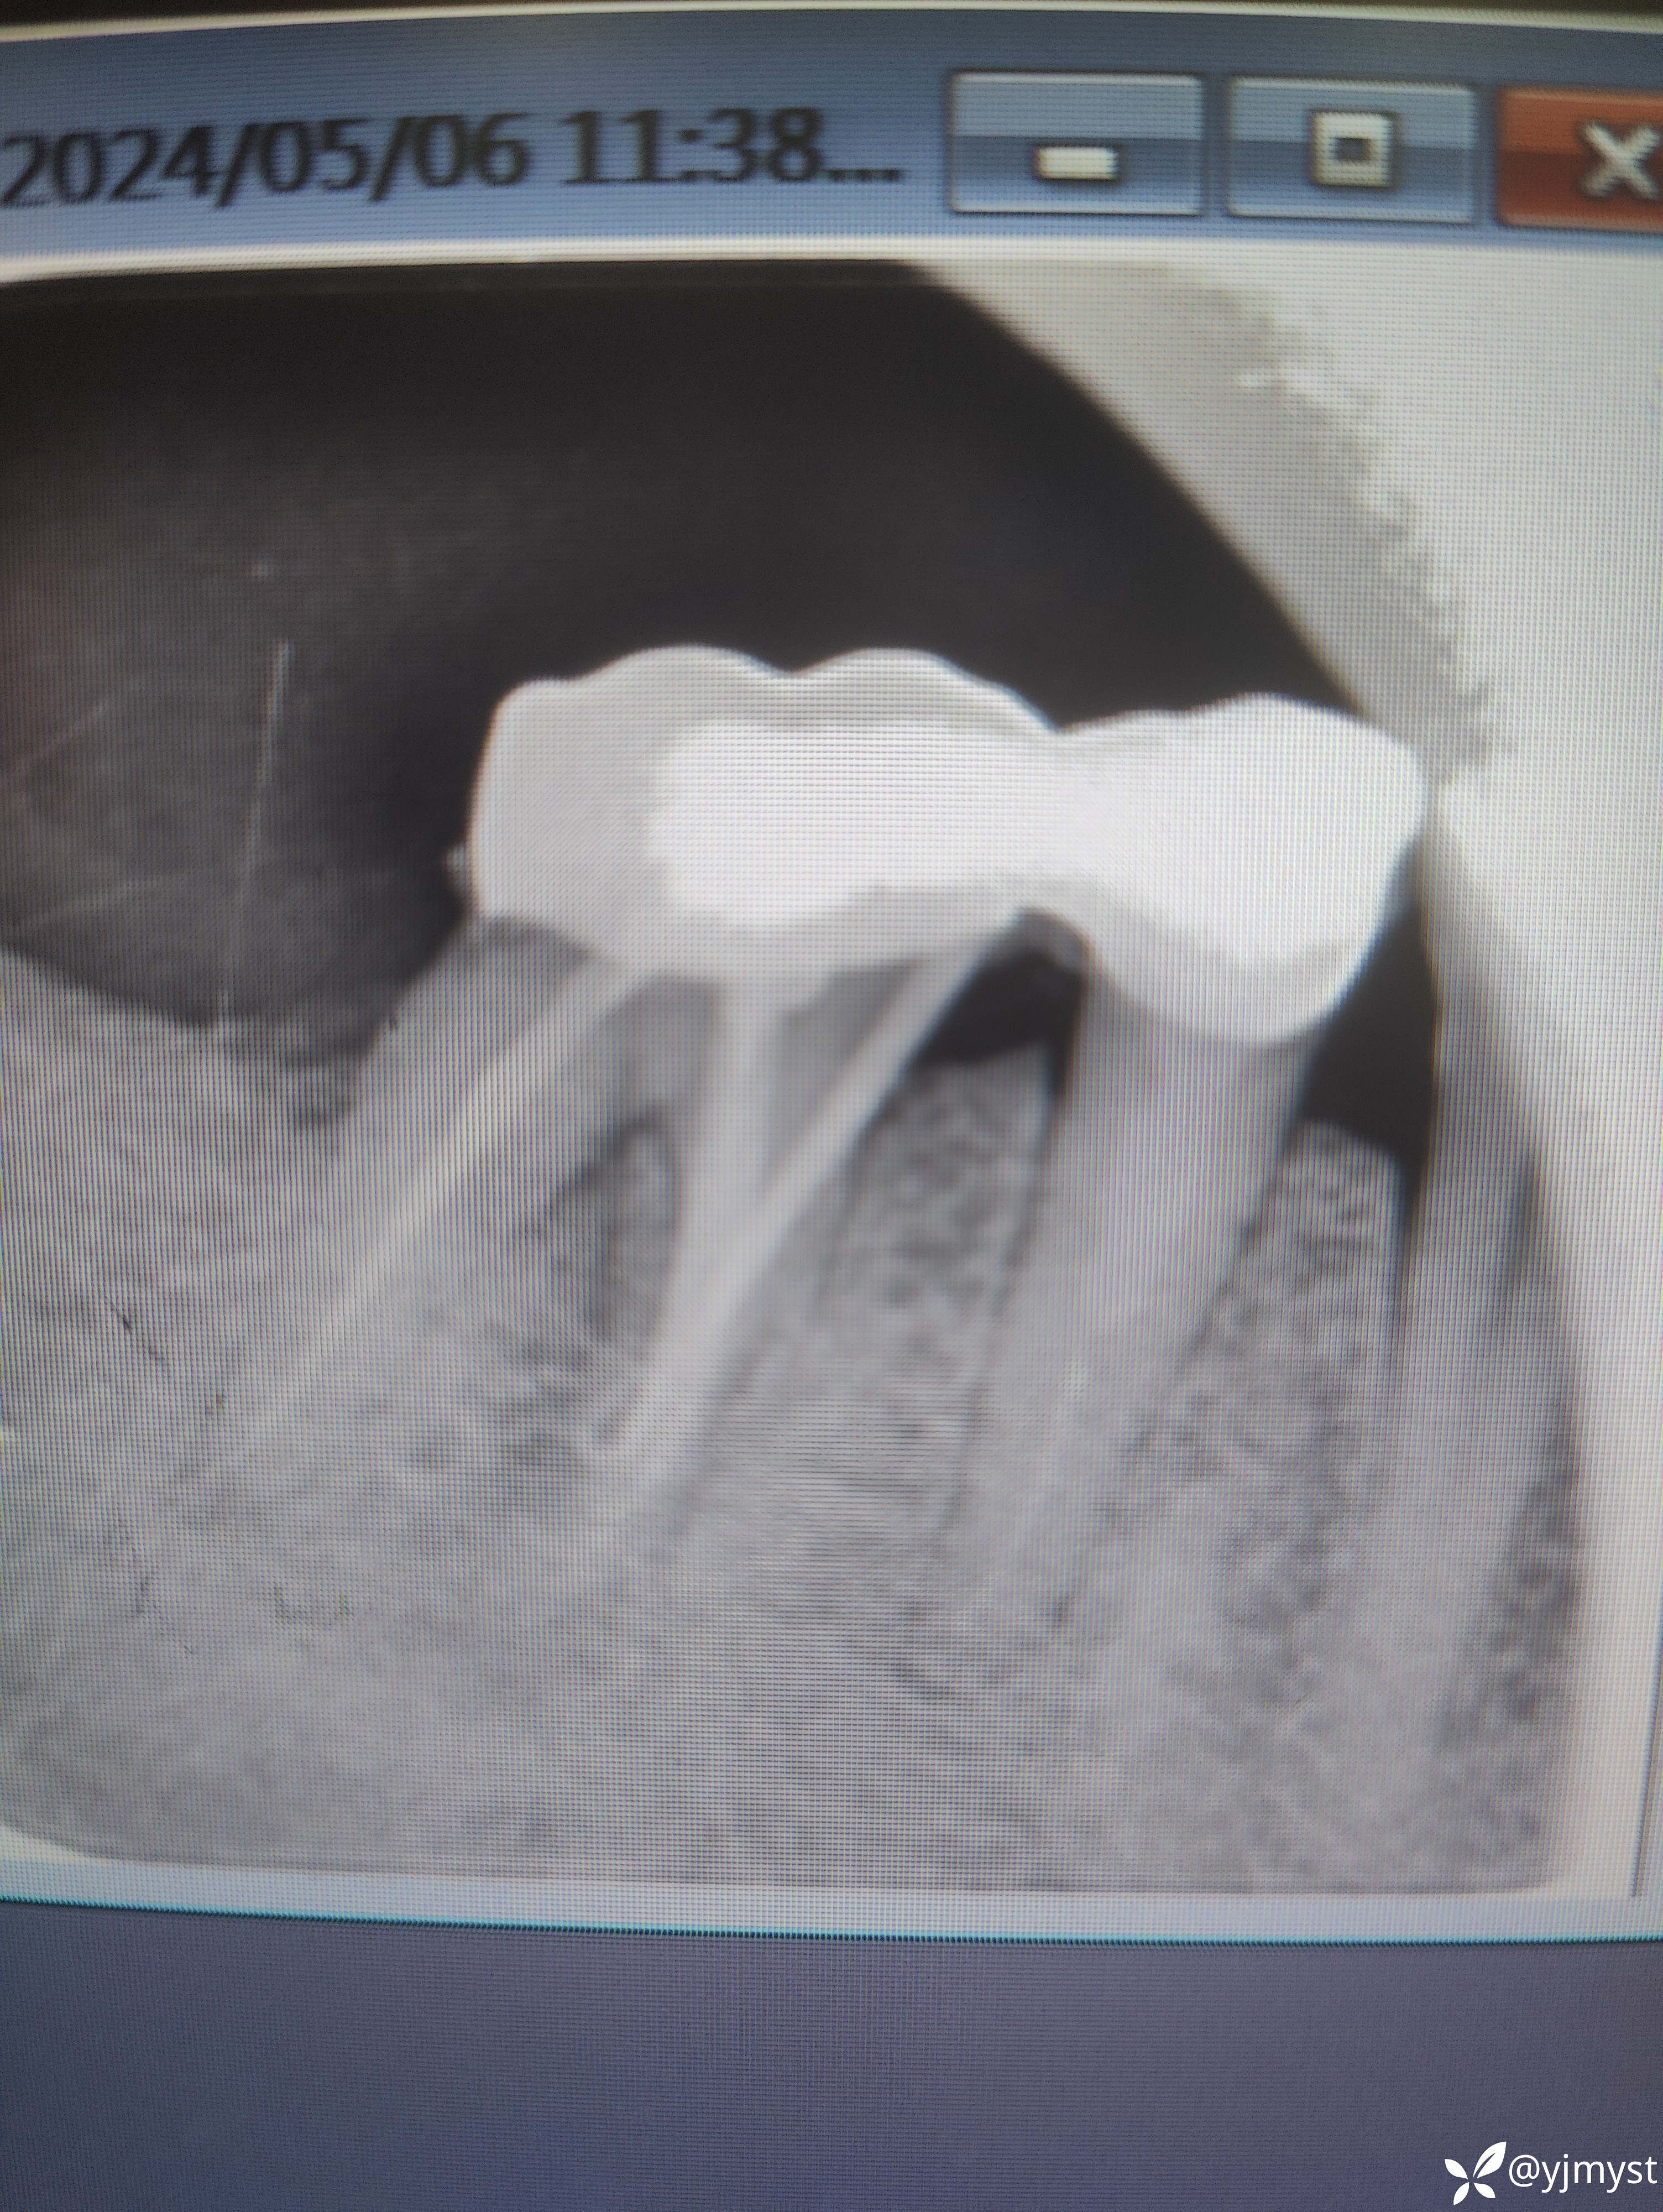

检查发现45牙、46牙LAVA联冠,无松动,拍CT示46牙近中根根周暗影,补拍一张瘘管插入牙胶尖的小牙片发现牙胶尖在近中牙根下段弯曲了,近颊某个位点牙周袋探诊深度为7mm,叩诊稍有不适,诊断牙周牙髓联合病变。跟患者交流说怀疑脓包来源可能既有牙周也有根管原因,提出了3个方案:①根管再治疗+牙周刮治②根尖手术进行倒预备倒充填③拔除做种植。